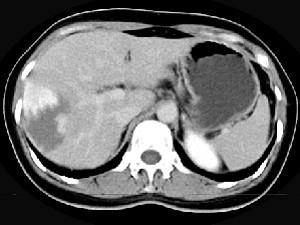

问题 女,38岁,无任何症状,体检发现肝右叶占位性病变,增强表现如图,最可能的诊断为 ( )

选项 A、肝脓肿 B、肝腺瘤 C、肝转移瘤 D、肝血管瘤 E、原发性肝癌

答案 D